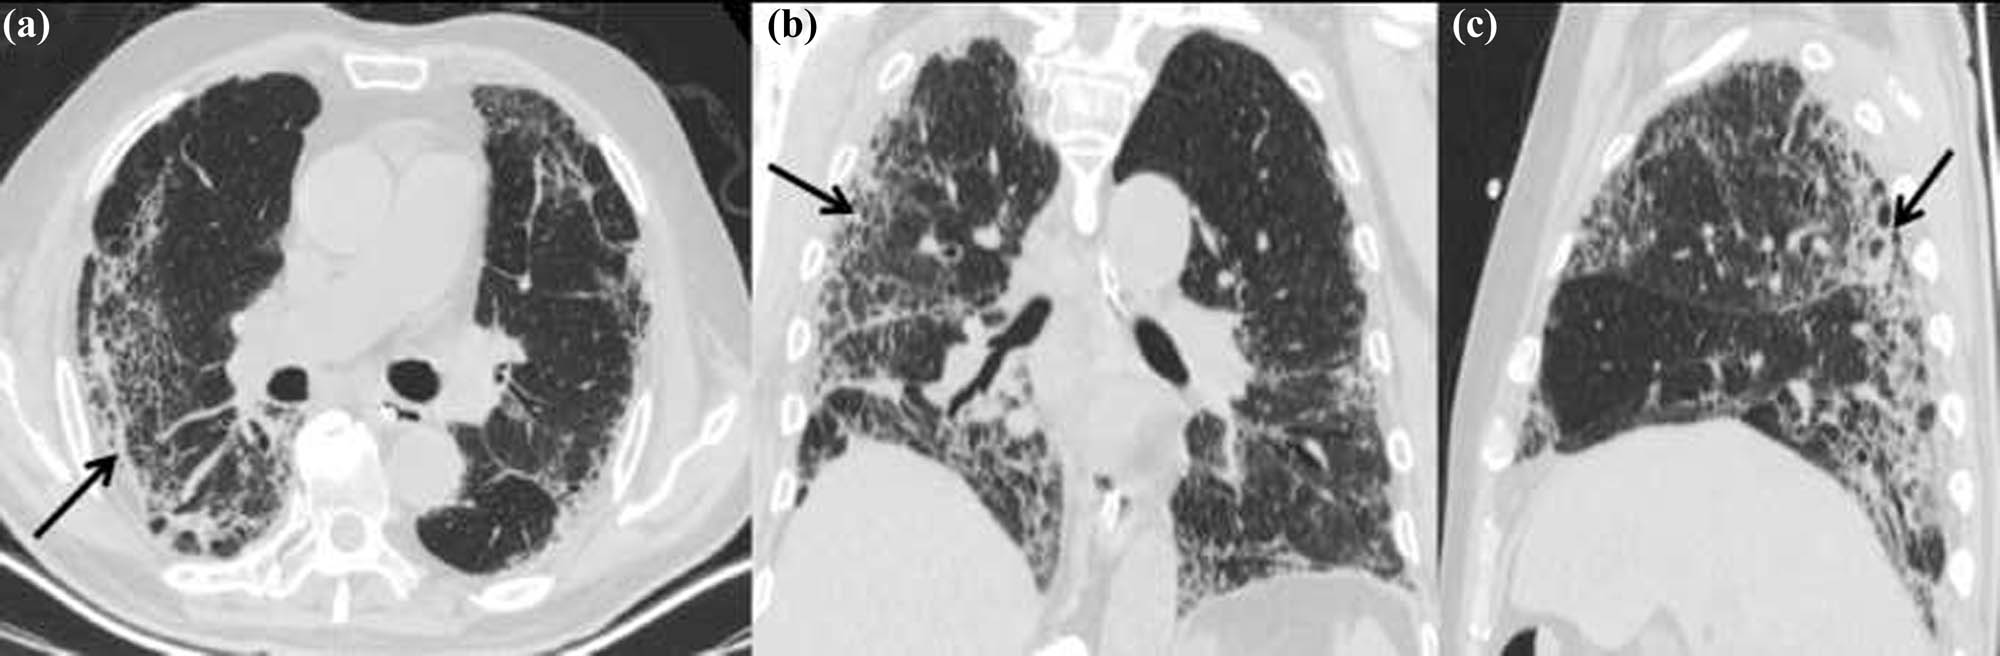

A 69-year-old man who suffered from fever, fatigue, myalgia, cough, and expectoration went to the hospital for medical treatment; temperature at admission: 38.2 ℃; heart rate: 78 times/min; respiration: 22 times/min; and blood pressure: 142/75 mm Hg. The patient stated that he had traveled back to Harbin from Wuhan, Hubei Province, by aircraft 1 day before and returned to Mudanjiang city, Heilongjiang Province from Harbin by high-speed railway. The patient stated that he had a smoking history, no drinking history, and suffered hypertension. The results of laboratory examination after admission are as follows: normal leucocyte count (6.17 × 109/L), decreased lymphocyte count (0.72 × 109/L), increased C-reactive protein (64.5 mg/L), increased erythrocyte sedimentation rate (28 mm/h), and increased D-dimer (1.44 µg/mL). CT examination showed that the two lungs had a large area of ground-glass opacity (GGO) and a small area of patchy consolidation. The lesions had an obscure boundary, which distributed mainly in a subpleural area. CT images also reveal “air bronchography sign,” enlargement of mediastinal lymph nodes, and bilateral pleura thickening. The patient was admitted to the hospital for antiviral treatment and symptomatic supportive treatment.

The main CT imaging feature of COVID-19 includes bilateral GGO, mainly with the subpleural distribution. The imaging of mild cases shows the focal distribution. CT findings of severe cases show the diffuse distribution in double lung fields such as the case we reported. GGO can be accompanied by consolidation, which is mainly seen in critically ill patients with “white lung” changes [2]. “Air bronchography sign,” thickened vascular shadow were seen in lesions. Thickened interlobular septa and “crazy-paving pattern” can also be seen in CT imaging [3]. Because the patient we reported is under the severe condition, lesions on the CT are quite obvious. CT imaging shows large areas of GGO, which is a classical manifestation. With the development of the disease, fibrous changes can be formed, which is manifested as a grid shadow. Fibrous changes illustrate the destruction of lung tissues, especially in severe cases. In the third CT examination of our patient, fibrous stripes exist definitely. Some patients have enlarged mediastinal lymph nodes, and pleural effusion is rare. There are also a small number of patients with negative CT manifestations, which should be noted [4]; thus, the diagnosis of COVID-19 should not depend only on radiology.

COVID-19 can be divided into four stages according to its imaging characteristics and lung involved: early stage, progressive stage, critical stage, and remission stage [3]. We report the case in a dynamic course. As the patient was admitted to the hospital in a critical stage, we did not obtain the classical imaging of early stage and progressive stage. However, we can see the recovery of the patient by CT imaging. The areas of GGO reduced obviously as the lesions were absorbed. The fibrous changes emerged later (Figures 1–4).

First CT scans of the patient (a: axial noncontrast CT image; b: coronal thin-section noncontrast CT image; and c: sagittal thin-section noncontrast CT image) showing large areas of GGO distributed mainly in subpleural (black arrows), thickened vascular shallow (white arrow), and bronchus shallow (white asterisk).